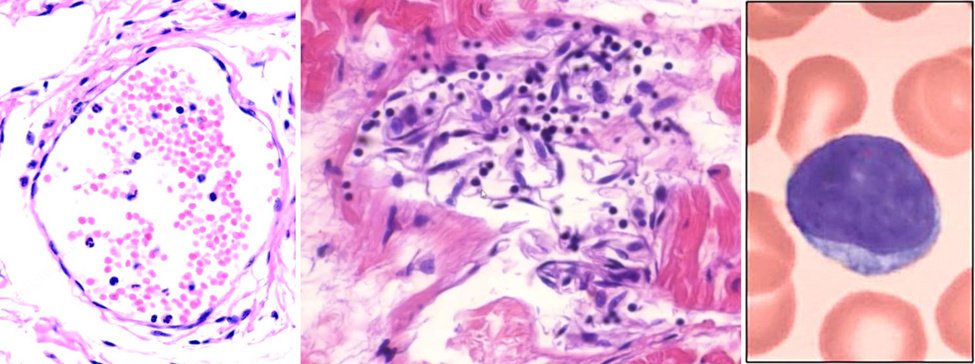

Vediamo l’espressione della proteina spike nelle arteriole (piccole arterie; a sinistra) così come nelle venule (piccole vene) e nei capillari (a destra). L’espressione è più prominente nello strato cellulare più interno, l’ endotelio . Questo rende le cellule endoteliali “anatre sedute” per un attacco da parte del sistema immunitario.

9. Stripping endoteliale e distruzione di un piccolo vaso sanguigno dopo la vaccinazione

Passiamo ora all’evidenza dell’attacco immunitario alle cellule endoteliali che producono la proteina spike. A sinistra, una venula normale, delimitata da un endotelio intatto e contenente all’interno alcuni globuli rossi e pochi globuli bianchi (colorati in blu).

L’immagine al centro mostra una venula che viene attaccata e distrutta dal sistema immunitario. Il contorno si sta già dissolvendo e le cellule endoteliali a forma di fuso (e gonfie) si sono staccate dalla parete del vaso. Inoltre, vediamo i linfociti, le piccole cellule con nuclei scuri e rotondi e con pochissimo citoplasma attorno a loro; un singolo linfocita (a un ingrandimento molto più elevato) è mostrato sulla destra.

I linfociti sono la spina dorsale del sistema immunitario specifico: ogni volta che gli antigeni vengono riconosciuti e gli anticorpi vengono prodotti, ciò viene fatto dai linfociti. Anche tra i linfociti troviamo le cellule T citotossiche e le cellule natural killer, che servono a uccidere le cellule infettate dal virus, o che le sembrano infette, perché sono state costrette a produrre una proteina virale da un cosiddetto vaccino.

Una funzione cruciale dell’endotelio è prevenire la coagulazione del sangue. Pertanto, se l’endotelio è danneggiato, come in questa immagine, ei tessuti al di là di esso entrano in contatto con il sangue, ciò attiverà automaticamente la coagulazione del sangue.